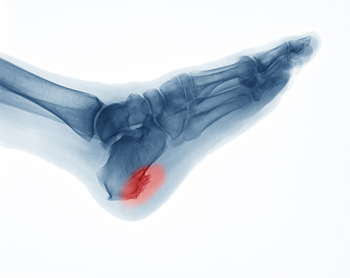

Heel spurs, also referred to as calcaneal spurs or osteophytes, are calcium deposits that develop on the heel bone over time. They typically form in response to chronic strain or tears to the plantar fascia tissue that connects the heel with the toes, or to damage to the heel bone membrane. Other factors that may contribute to heel spurs developing include obesity, wearing improper shoes, age, trauma, training on hard surfaces, or having plantar fasciitis (damage to the plantar fascia) or certain medical conditions. Heel spurs develop on the part of the heel that is closest to the arch, and they point towards the middle of the foot. Heel spurs can be up to a half inch long and are usually only detectable with an X-ray. Heel spurs are usually not painful. When they are, a podiatrist can treat them with rest, ice, orthotic devices and/or shoes, anti-inflammatory medication, cortisone injections, or even surgery if necessary (to remove the spurs).

Heel spurs are formed by calcium deposits on the back of the foot where the heel is. This can also be caused by small fragments of bone breaking off one section of the foot, attaching onto the back of the foot. Heel spurs can also be bone growth on the back of the foot and may grow in the direction of the arch of the foot.

Heel spurs are calcium deposits that cause bone protrusions on the heel bone. Heel spurs are usually associated with plantar fasciitis, which occurs when the plantar fasciitis in the foot becomes inflamed. Typically, heel spurs don’t cause any symptoms. However, they can produce chronic or intermittent heel pain. Those who have had the condition often describe the irritation as a stabbing pain.